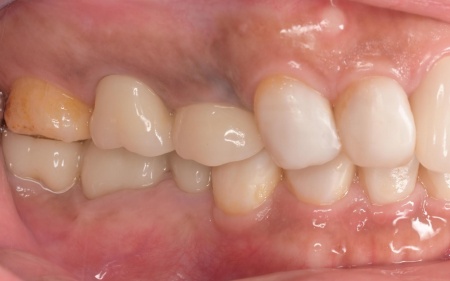

矯正期間終了後は、被せ物による治療に移行します。

上顎の前歯2本ずつと奥歯4本(左右中切歯・第2小臼歯・第1大臼歯)、下顎の奥歯7本(左第1小臼歯・左右第2小臼歯・第1大臼歯・第2大臼歯)には、見た目が自然なセラミックの被せ物「ジルコニアクラウン」を装着しました。

ジルコニアは、金属を使わないため金属アレルギーの心配が少ない点、人工ダイヤモンドと呼ばれるほどの強度をもち噛む力の強い奥歯にも適している点がメリットです。

加えて、上前歯4本(左右側切歯・犬歯)と下前歯5本(左右中切歯・側切歯・右下犬歯)は、ダイレクトクラウンによる修復を行いました。

ダイレクトクラウンとは、レジン(樹脂)を用いて直接歯の形を作り上げていく治療方法です。

歯を削る量が少ない、色や形を細かく調整しながら仕上げられる、治療後は必要に応じて微調整がしやすいなどのメリットがあります。